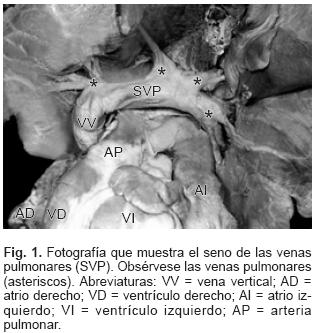

En todos los especímenes el SVP estuvo independiente, separado del atrio izquierdo y ubicado por detrás y un poco por encima de esta cámara cardíaca incompleta y pequeña (Figs. 1 y 2). El SVP se continuó con un vaso colector que siguió diferentes trayectos según el sitio de conexión anómala; en el tipo a vena cava superior el colector ascendió por detrás del bronquio derecho o del izquierdo según la posición de esa vena; en dos especímenes la obstrucción del colector fue intrínseca por estrechez del mismo en el sitio de su desembocadura (Figs. 3A y 4) y en un espécimen el colector siguió un trayecto anómalo entre la rama derecha de la arteria pulmonar y el bronquio derecho lo que provocó obstrucción extrínseca en el mismo (Fig. 3B). En el sitio de conexión anómala a la vena vertical el SVP recibió las venas de ambos pulmones y a través de un colector corto se continuó con la vena vertical ubicada del lado izquierdo, ésta a su vez lo hizo con el tronco venoso braquiocefálico izquierdo que desembocó en la vena cava superior y ésta en el atrio derecho (Fig. 5); en un espécimen existió obstrucción intrínseca en la vena vertical (Fig. 6).